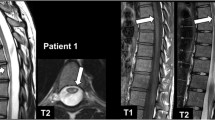

Magnetic resonance imaging (MRI) is a clinically important tool for diagnosing several neurological diseases such as the multiple sclerosis (MS). Brain MRI has always facilitated the examination of the MS pathology. Moreover, spinal cord MRI is greatly suggested for the management of such disease, even though the use of conventional spinal cord MRI can be a challenging task. In fact, it is a long and fine organ that has some mobility and that suffers from breathing artifacts, low contrast, heartbeat and cerebro-spinal fluid flows. In this study, to identify spinal cord damage in MS patient, an adaptive MRI contrast enhancement (CE), called the LL-GAGC method, is proposed. This novel technique is based on a combination of the adaptive gamma correction and the discrete wavelet transform with singular value decomposition algorithms. The main reason of this association is to enhance adaptively the contrast of dark MR images while preserving edge information from any distortion. A large database formed by 112 T2-w spinal cord MR images was examined for assessment of the proposed LL-GAGC CE method. Qualitative and quantitative evaluations demonstrated that our proposed algorithm performs well in enhancing the contrast of dark MR images with the benefit of preserving brightness information and edges details.

Sahnoun, M., Kallel, F., Dammak, M. et al. Spinal cord MRI contrast enhancement using adaptive gamma correction for patient with multiple sclerosis. SIViP 14, 377–385 (2020). https://doi.org/10.1007/s11760-019-01561-x